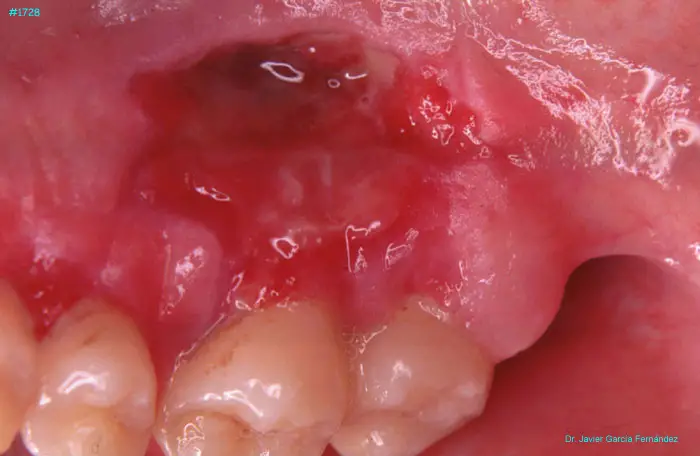

Atlas of Surgical Techniques in Periodontics. Chapter IV. Atlas de Técnicas Quirúrgica en Periodoncia

image 236